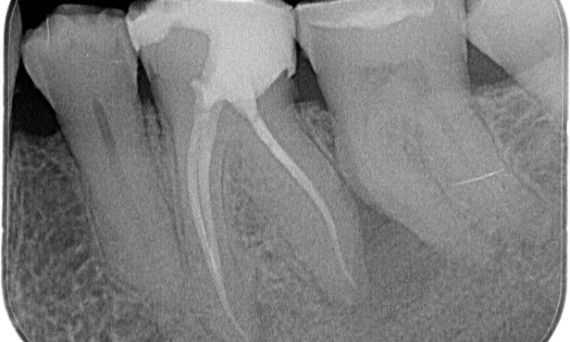

Na: TruNatomy werd voor deze casus gekozen om een cariësgerichte benadering en een focus op pericervicale dentineconservering mogelijk te maken, vooral op het mesiale aspect waar de tand een meer minimale restauratie had.

Na: De toegangsholte werd zo conservatief mogelijk gerealiseerd. TruNatomy was het voorkeurssysteem, vanwege de jonge leeftijd van de patiënt. We moesten de dentine zo veel mogelijk behouden, om de tand beter in staat te stellen occlusale belasting te doorstaan en de levensduur van de uiteindelijke restauratie te verlengen.